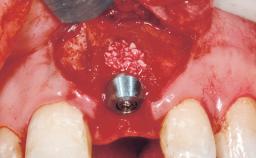

A 30-year-old female patient had lost tooth 21 and was referred to our clinic for consultation and treatment. Due to advanced apical infection, tooth 21 had been extracted two months earlier at another clinic and an acrylic-resin tooth had been bonded to the adjacent teeth. The patient desired implant treatment to avoid any damage to the adjacent natural teeth. While the patient had no history of any systemic disorder, she was a heavy smoker and exhibited medium to advanced periodontitis in the entire jaw. After the initial treatment to achieve a pocket probing depth of less than 4 mm and no bleeding on probing, a decrease in the height of the papillae mesial and distal to the extraction site and overall gingival recession were observed.

Type of Implants One-Piece|Reduced-Diameter

Bone Augmentation Horizontal|Staged

Augmentation Materials Autogenous chips|Membrane

Placement Protocol Early or late implant placement

Bone Volume Deficient horizontally, requiring prior grafting